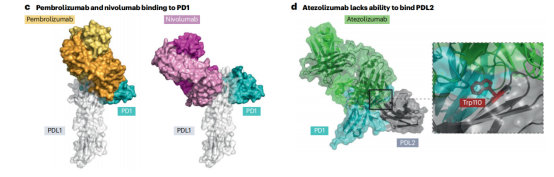

免疫检查点通过阻断抗体抑制负调节T细胞的途径,从而使细胞毒性T细胞重新活化,杀死癌细胞。已获得FDA或EMA批准的治疗性抗体靶向的三种蛋白或途径是CTLA4,PD1-PDL1和LAG3。PD1阻断抗体是目前使用最广泛的免疫检查点抑制剂。7种已获批的PD1阻断抗体和目前正在临床试验的两种使用IgG4格式,与IgG1同型相比,它不能有效激活补体级联,Fc受体结合较弱。因此,IgG4格式可能保护表达PD1的效应T细胞不被ADCC或CDC无意中杀死。所有IgG4抗体都携带S228P突变以防止Fab臂交换。通过结果生物学分析发现,PD1的2种阻断抗体pembrolizumab和nivolumab结合PD1的不同表位,并且与配体PDL1结合位点重叠,从而阻止PD1-PDL1相互作用。PDL1靶向抗体与PDL1和PDL2复合物的晶体结构鉴定了PDL2中一个关键残基(Trp100),该残基阻碍抗PDL1抗体与PDL2的结合,并提供了PDL1和PDL2之间的选择性机制。

两种CTLA4靶向抗体Ipilimumab和Tremeli-mumab具有相似的结合表位,可以有效地与天然配体CD80和CD86竞争。